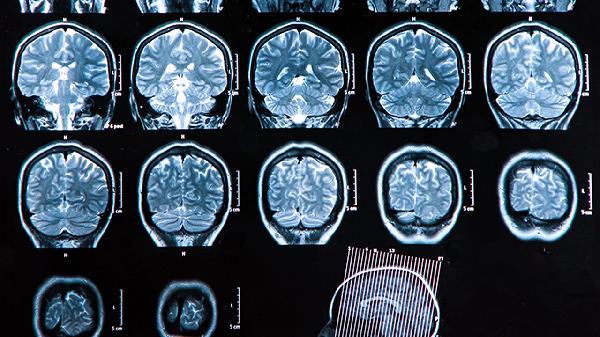

长期脑雾状态需排查甲状腺功能减退、脑供血不足等器质性疾病。日常保持适度有氧运动促进脑部血液循环,工作间歇可做眼保健操缓解视疲劳。饮食注意控制精制糖摄入,适量增加核桃、深海鱼等富含omega-3脂肪酸的食物。若症状持续两周无改善,建议神经内科就诊进行脑电图或经颅多普勒检查。